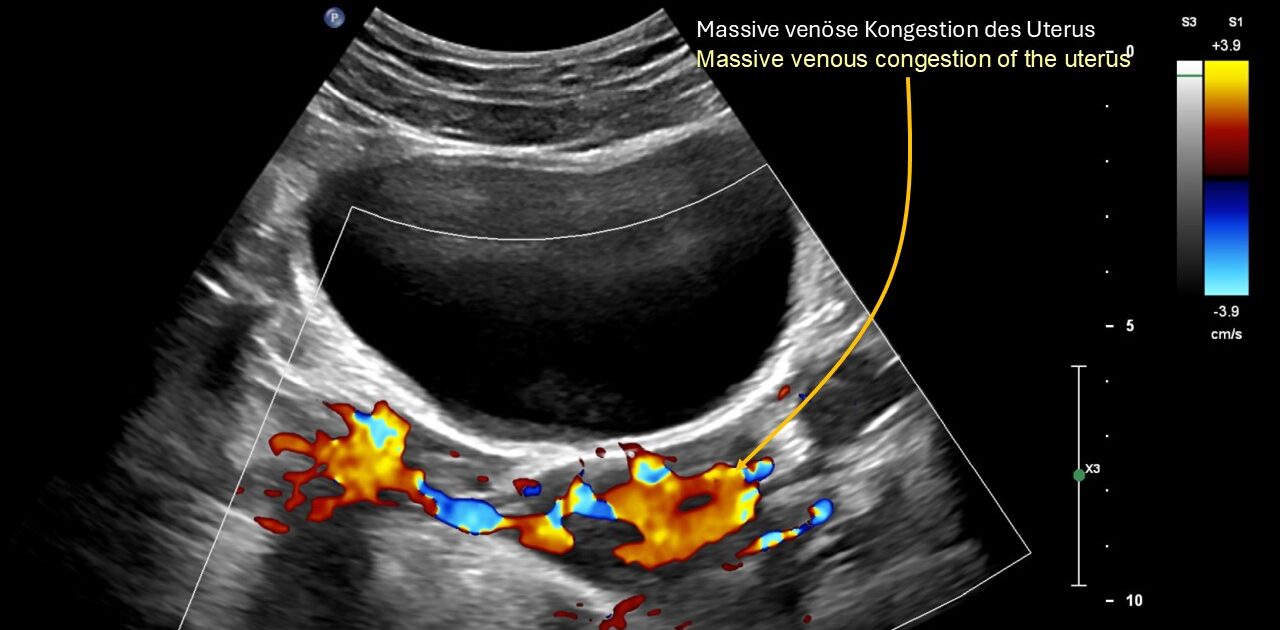

- Es bestand eine vollständige Kompression der Vena iliaca communis sinistra, die zu einer massiven Stauung der Beckenorgane geführt hatte

Die spastische Innenrotation des linken Beins wird durch eine venöse Stauung des Rückenmarks im Wirbelkanal verursacht, während die entlang des Ischiasnervs ausstrahlenden Schmerzen durch eine schwere Obstruktion des Abflusses in der linken inneren Beckenvene verursacht werden, die den venösen Rückfluss aus dem Ischiasnerv über die linke untere Gesäßvene fast vollständig stoppt.

Die Schmerzen bei der Nahrungsaufnahme ließen sich leicht durch den erhöhten Druck erklären, den der sich füllende und vergrößerte Magen auf die massiv gestaute linke Nierenvene hinter dem Magen während der oralen Nahrungsaufnahme ausübte. Aus klinischer Sicht bestand auch eine Kompression des Zwölffingerdarms (Wilkie-Syndrom), die zu sofortigem Erbrechen nach der Nahrungsaufnahme in Kombination mit starken Schmerzen im Oberbauch führte.